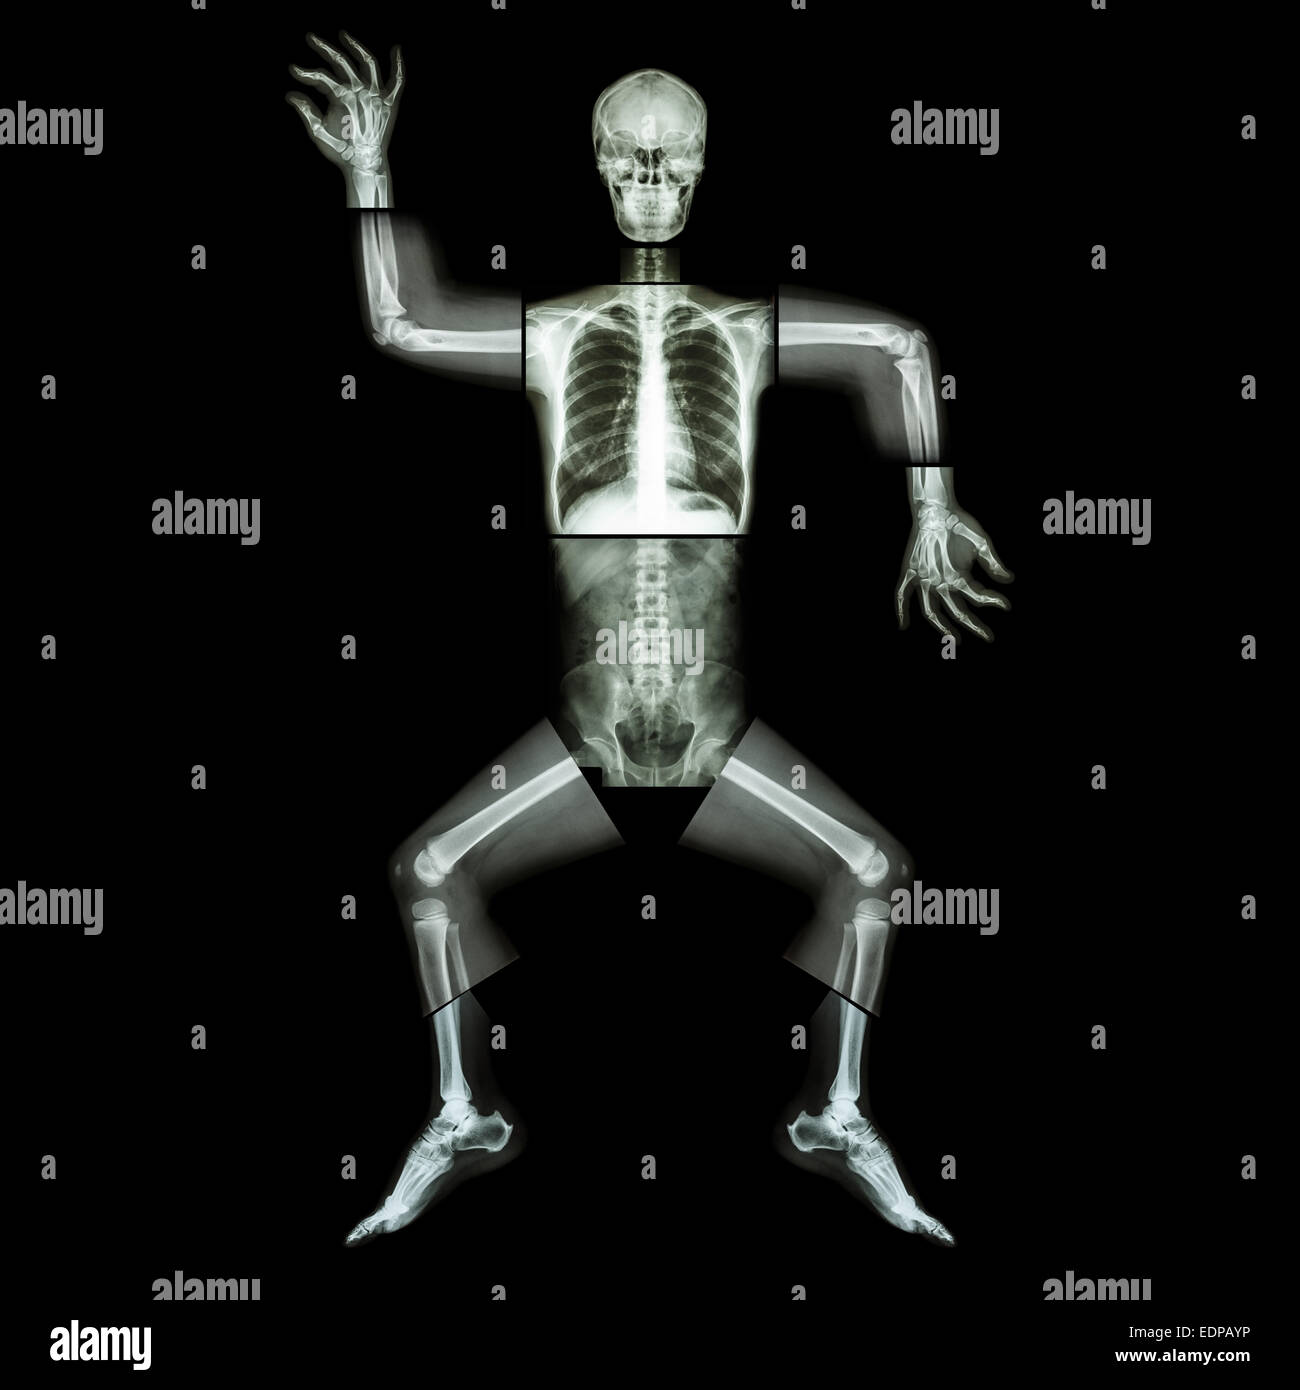

Marathon (les droits de l'os est en marche) ,(corps entier x-ray : tête, cou, bras, épaule, coude, avant-bras, main, doigt ,,commune thorax ,ab Banque D'Imageshttps://www.alamyimages.fr/image-license-details/?v=1https://www.alamyimages.fr/photo-image-marathon-les-droits-de-l-os-est-en-marche-corps-entier-x-ray-tete-cou-bras-epaule-coude-avant-bras-main-doigt-commune-thorax-ab-77324375.html

Marathon (les droits de l'os est en marche) ,(corps entier x-ray : tête, cou, bras, épaule, coude, avant-bras, main, doigt ,,commune thorax ,ab Banque D'Imageshttps://www.alamyimages.fr/image-license-details/?v=1https://www.alamyimages.fr/photo-image-marathon-les-droits-de-l-os-est-en-marche-corps-entier-x-ray-tete-cou-bras-epaule-coude-avant-bras-main-doigt-commune-thorax-ab-77324375.htmlRFEDPC0R–Marathon (les droits de l'os est en marche) ,(corps entier x-ray : tête, cou, bras, épaule, coude, avant-bras, main, doigt ,,commune thorax ,ab

Marathon (les droits de l'os est en marche) ,(corps entier x-ray : tête, cou, bras, épaule, coude, avant-bras, main, doigt ,,commune thorax ,ab Banque D'Imageshttps://www.alamyimages.fr/image-license-details/?v=1https://www.alamyimages.fr/photo-image-marathon-les-droits-de-l-os-est-en-marche-corps-entier-x-ray-tete-cou-bras-epaule-coude-avant-bras-main-doigt-commune-thorax-ab-77324374.html

Marathon (les droits de l'os est en marche) ,(corps entier x-ray : tête, cou, bras, épaule, coude, avant-bras, main, doigt ,,commune thorax ,ab Banque D'Imageshttps://www.alamyimages.fr/image-license-details/?v=1https://www.alamyimages.fr/photo-image-marathon-les-droits-de-l-os-est-en-marche-corps-entier-x-ray-tete-cou-bras-epaule-coude-avant-bras-main-doigt-commune-thorax-ab-77324374.htmlRFEDPC0P–Marathon (les droits de l'os est en marche) ,(corps entier x-ray : tête, cou, bras, épaule, coude, avant-bras, main, doigt ,,commune thorax ,ab

Marathon (les droits de l'os est en marche) ,(corps entier x-ray : tête, cou, bras, épaule, coude, avant-bras, main, doigt ,,commune thorax ,ab Banque D'Imageshttps://www.alamyimages.fr/image-license-details/?v=1https://www.alamyimages.fr/photo-image-marathon-les-droits-de-l-os-est-en-marche-corps-entier-x-ray-tete-cou-bras-epaule-coude-avant-bras-main-doigt-commune-thorax-ab-77323572.html

Marathon (les droits de l'os est en marche) ,(corps entier x-ray : tête, cou, bras, épaule, coude, avant-bras, main, doigt ,,commune thorax ,ab Banque D'Imageshttps://www.alamyimages.fr/image-license-details/?v=1https://www.alamyimages.fr/photo-image-marathon-les-droits-de-l-os-est-en-marche-corps-entier-x-ray-tete-cou-bras-epaule-coude-avant-bras-main-doigt-commune-thorax-ab-77323572.htmlRFEDPB04–Marathon (les droits de l'os est en marche) ,(corps entier x-ray : tête, cou, bras, épaule, coude, avant-bras, main, doigt ,,commune thorax ,ab

Marathon (les droits de l'os est en marche) ,(corps entier x-ray : tête, cou, bras, épaule, coude, avant-bras, main, doigt ,,commune thorax ,ab Banque D'Imageshttps://www.alamyimages.fr/image-license-details/?v=1https://www.alamyimages.fr/photo-image-marathon-les-droits-de-l-os-est-en-marche-corps-entier-x-ray-tete-cou-bras-epaule-coude-avant-bras-main-doigt-commune-thorax-ab-77324380.html

Marathon (les droits de l'os est en marche) ,(corps entier x-ray : tête, cou, bras, épaule, coude, avant-bras, main, doigt ,,commune thorax ,ab Banque D'Imageshttps://www.alamyimages.fr/image-license-details/?v=1https://www.alamyimages.fr/photo-image-marathon-les-droits-de-l-os-est-en-marche-corps-entier-x-ray-tete-cou-bras-epaule-coude-avant-bras-main-doigt-commune-thorax-ab-77324380.htmlRFEDPC10–Marathon (les droits de l'os est en marche) ,(corps entier x-ray : tête, cou, bras, épaule, coude, avant-bras, main, doigt ,,commune thorax ,ab

La danse aérobie(os humains est la danse),(corps entier x-ray : tête, cou, thorax, bras, épaule, coude, avant-bras, main, doigt joint , Banque D'Imageshttps://www.alamyimages.fr/image-license-details/?v=1https://www.alamyimages.fr/photo-image-la-danse-aerobie-os-humains-est-la-danse-corps-entier-x-ray-tete-cou-thorax-bras-epaule-coude-avant-bras-main-doigt-joint-77323560.html

La danse aérobie(os humains est la danse),(corps entier x-ray : tête, cou, thorax, bras, épaule, coude, avant-bras, main, doigt joint , Banque D'Imageshttps://www.alamyimages.fr/image-license-details/?v=1https://www.alamyimages.fr/photo-image-la-danse-aerobie-os-humains-est-la-danse-corps-entier-x-ray-tete-cou-thorax-bras-epaule-coude-avant-bras-main-doigt-joint-77323560.htmlRFEDPAYM–La danse aérobie(os humains est la danse),(corps entier x-ray : tête, cou, thorax, bras, épaule, coude, avant-bras, main, doigt joint ,

La danse aérobie(os humains est la danse),(corps entier x-ray : tête, cou, thorax, bras, épaule, coude, avant-bras, main, doigt joint , Banque D'Imageshttps://www.alamyimages.fr/image-license-details/?v=1https://www.alamyimages.fr/photo-image-la-danse-aerobie-os-humains-est-la-danse-corps-entier-x-ray-tete-cou-thorax-bras-epaule-coude-avant-bras-main-doigt-joint-77323562.html

La danse aérobie(os humains est la danse),(corps entier x-ray : tête, cou, thorax, bras, épaule, coude, avant-bras, main, doigt joint , Banque D'Imageshttps://www.alamyimages.fr/image-license-details/?v=1https://www.alamyimages.fr/photo-image-la-danse-aerobie-os-humains-est-la-danse-corps-entier-x-ray-tete-cou-thorax-bras-epaule-coude-avant-bras-main-doigt-joint-77323562.htmlRFEDPAYP–La danse aérobie(os humains est la danse),(corps entier x-ray : tête, cou, thorax, bras, épaule, coude, avant-bras, main, doigt joint ,

La danse aérobie(os humains est la danse),(corps entier x-ray : tête, cou, thorax, bras, épaule, coude, avant-bras, main, doigt joint , Banque D'Imageshttps://www.alamyimages.fr/image-license-details/?v=1https://www.alamyimages.fr/photo-image-la-danse-aerobie-os-humains-est-la-danse-corps-entier-x-ray-tete-cou-thorax-bras-epaule-coude-avant-bras-main-doigt-joint-77323565.html

La danse aérobie(os humains est la danse),(corps entier x-ray : tête, cou, thorax, bras, épaule, coude, avant-bras, main, doigt joint , Banque D'Imageshttps://www.alamyimages.fr/image-license-details/?v=1https://www.alamyimages.fr/photo-image-la-danse-aerobie-os-humains-est-la-danse-corps-entier-x-ray-tete-cou-thorax-bras-epaule-coude-avant-bras-main-doigt-joint-77323565.htmlRFEDPAYW–La danse aérobie(os humains est la danse),(corps entier x-ray : tête, cou, thorax, bras, épaule, coude, avant-bras, main, doigt joint ,

La danse aérobie(os humains est la danse),(corps entier x-ray : tête, cou, thorax, bras, épaule, coude, avant-bras, main, doigt joint , Banque D'Imageshttps://www.alamyimages.fr/image-license-details/?v=1https://www.alamyimages.fr/photo-image-la-danse-aerobie-os-humains-est-la-danse-corps-entier-x-ray-tete-cou-thorax-bras-epaule-coude-avant-bras-main-doigt-joint-77323558.html

La danse aérobie(os humains est la danse),(corps entier x-ray : tête, cou, thorax, bras, épaule, coude, avant-bras, main, doigt joint , Banque D'Imageshttps://www.alamyimages.fr/image-license-details/?v=1https://www.alamyimages.fr/photo-image-la-danse-aerobie-os-humains-est-la-danse-corps-entier-x-ray-tete-cou-thorax-bras-epaule-coude-avant-bras-main-doigt-joint-77323558.htmlRFEDPAYJ–La danse aérobie(os humains est la danse),(corps entier x-ray : tête, cou, thorax, bras, épaule, coude, avant-bras, main, doigt joint ,